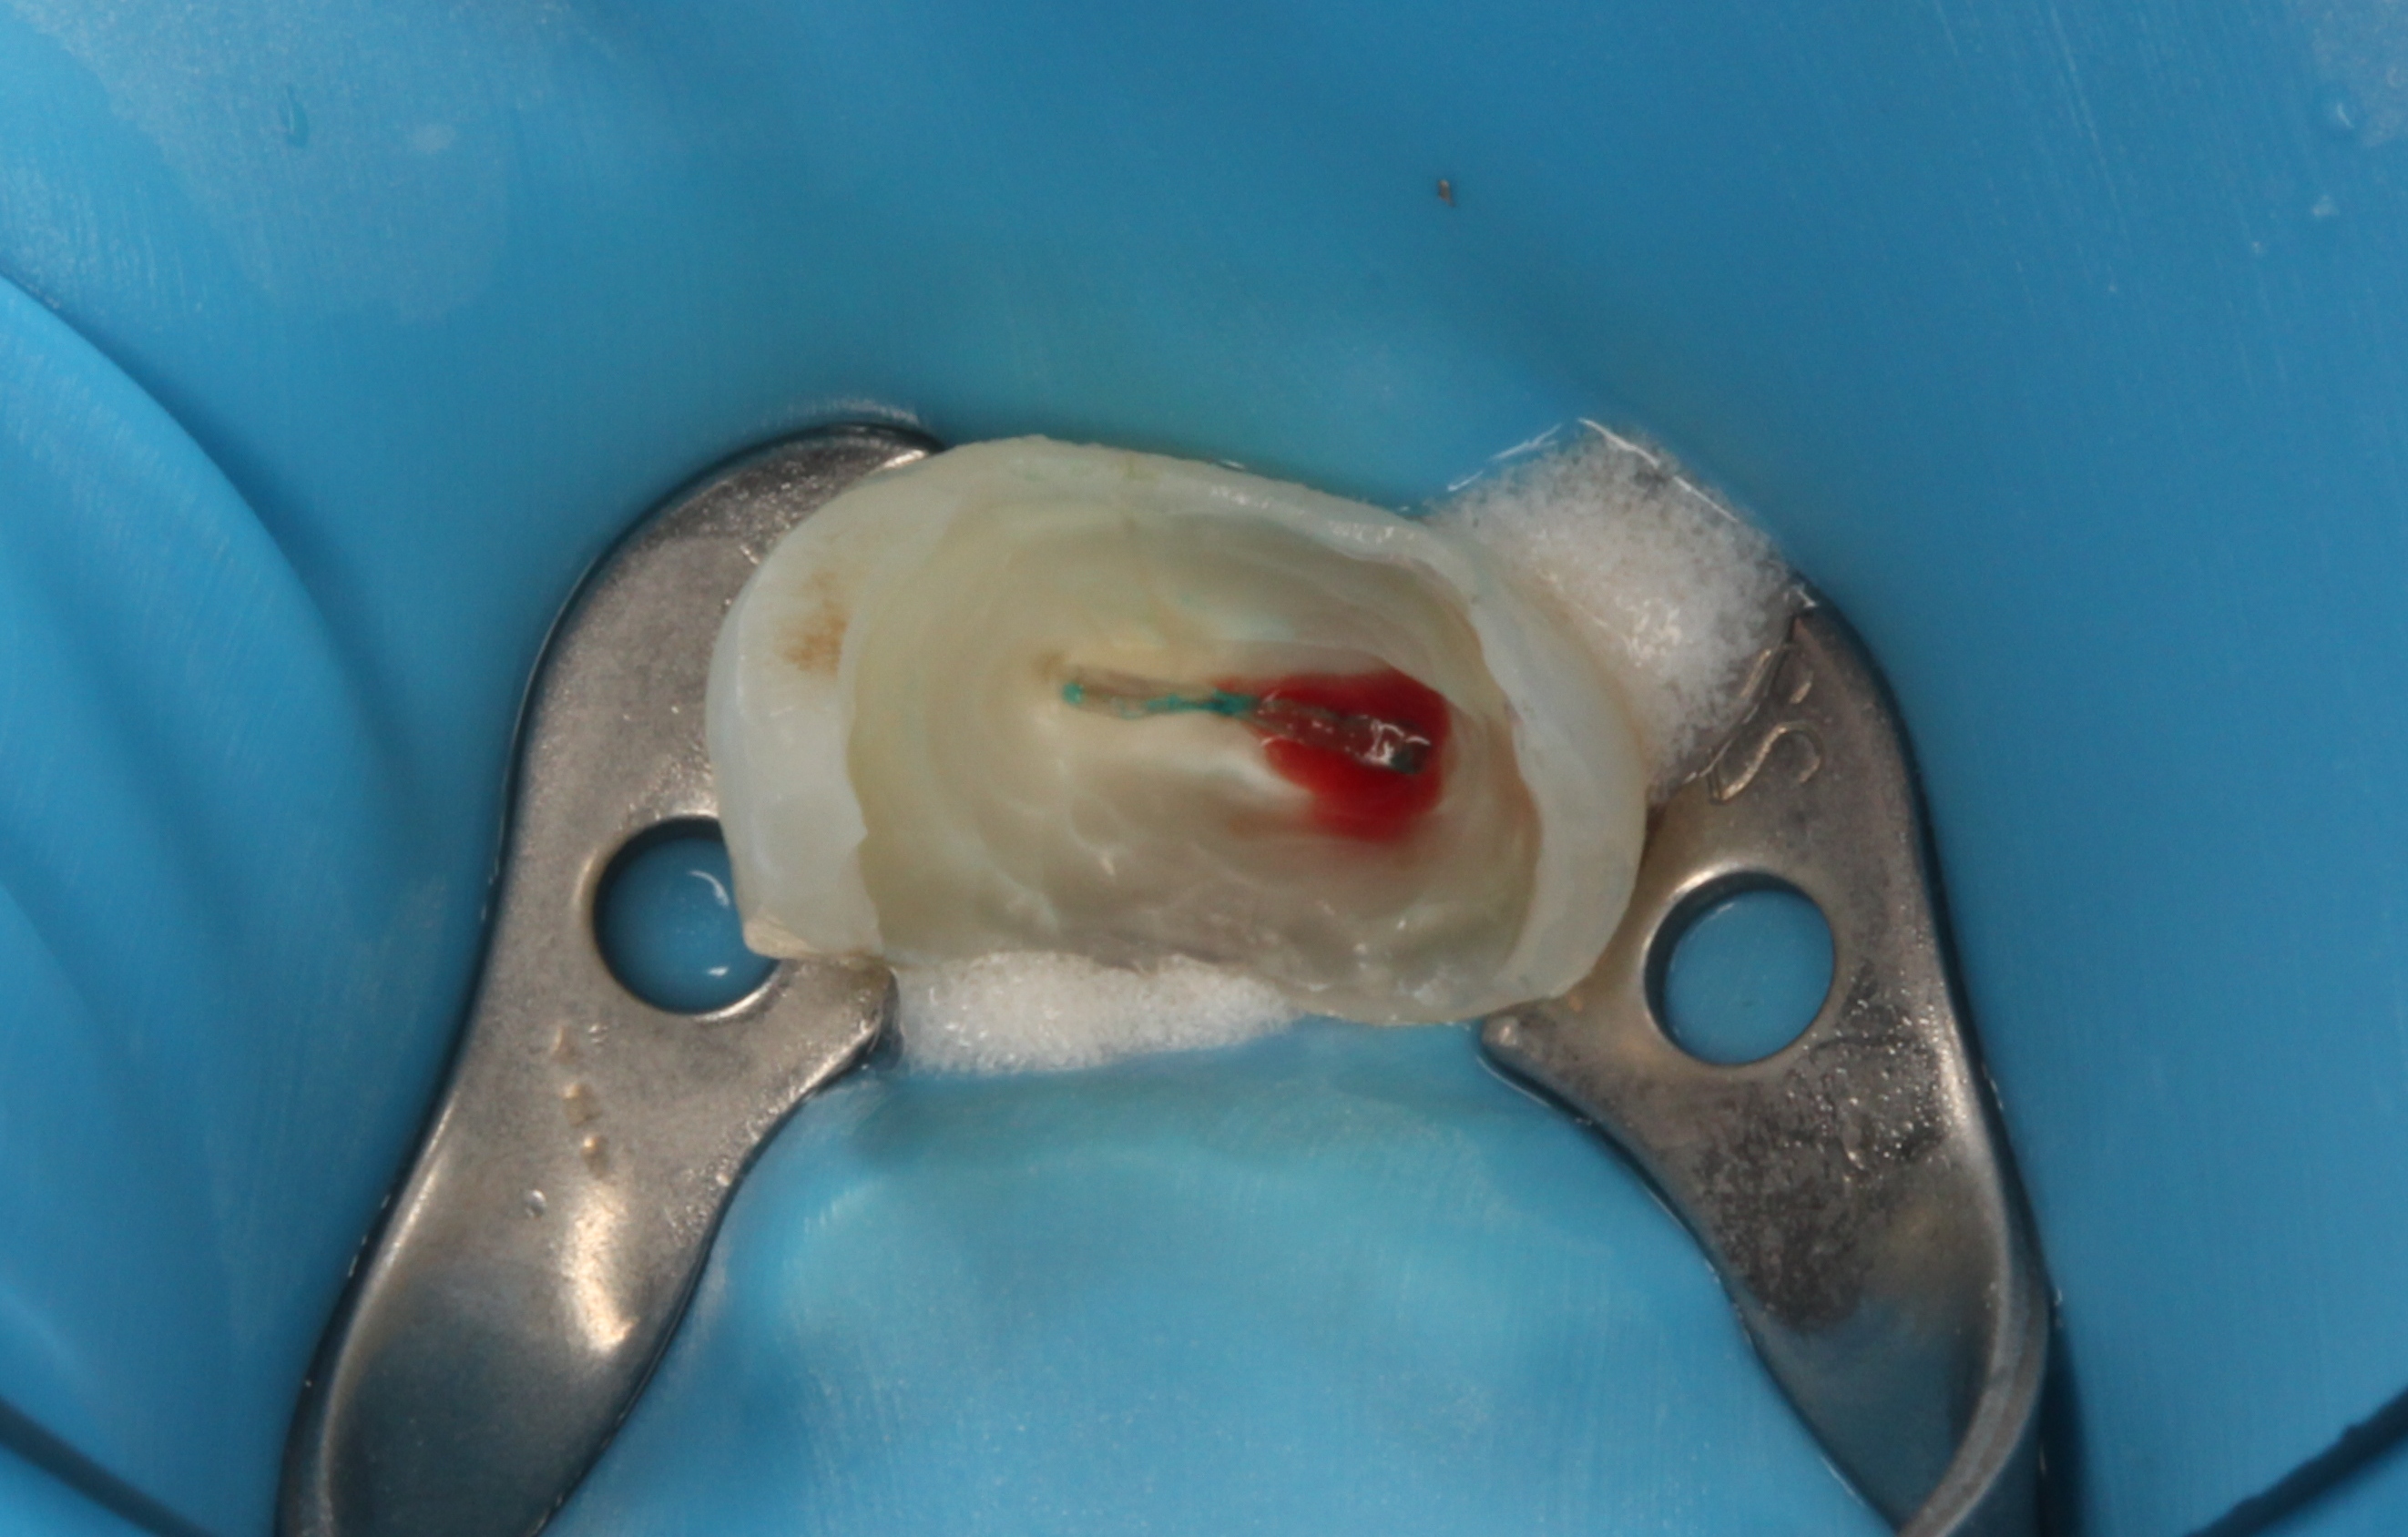

HOT ! 失敗しない歯髄保存療法 : 抜髄する前にもう一度歯髄診断をしよう Amazon.co.jp: 失敗しない歯髄保存療法: 抜髄する前にもう一度

失敗しない歯髄保存療法 : 抜髄する前にもう一度歯髄診断をしよう Amazon.co.jp: 失敗しない歯髄保存療法: 抜髄する前にもう一度の詳細情報

Amazon.co.jp: 失敗しない歯髄保存療法: 抜髄する前にもう一度。右下第二大臼歯 CTSに歯髄保存した症例│歯髄保存可能な歯と抜髄。歯髄保存療法 | 新橋駅徒歩4分、内幸町駅徒歩1分の歯医者 さとう。根管治療とは?一般的な治療法との比較 » 抜ける歯で未来を彩る。「失敗しない歯髄保存療法 : 抜髄する前にもう一度歯髄診断をしよう」中村 洋 / 須田 英明 / 興地 隆史定価: ¥ 10500#中村洋 #中村_洋 #須田英明 #須田_英明 #興地隆史 #興地_隆史 #本 #自然/医療・薬学・健康歯科口腔外科インプラント歯周外科歯内療法歯科医師歯科衛生士歯科雑誌歯科歯周治療